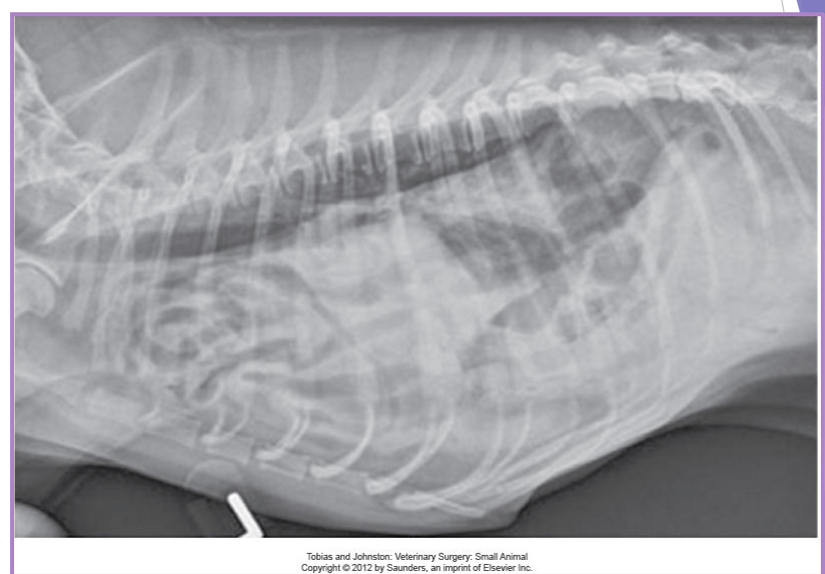

Traumatic and congenital diaphragmatic hernia

very common

continuity of the diaphragm is disrupted

abdominal organs migrate into the thorax

due to an alteration in pressure gradient

acute

shock, associated injuries, respiratory difficulty

chronic

respiratory dyspnea, exercise intolerance, nonspecific (ADR)

diagnostic evaluation

thoracic radiographs (65% accurate)

pleural effusion

gas/soft tissue opacity within the thoracic cavity

stomach against the diaphragm

loss of diaphragm silhouette